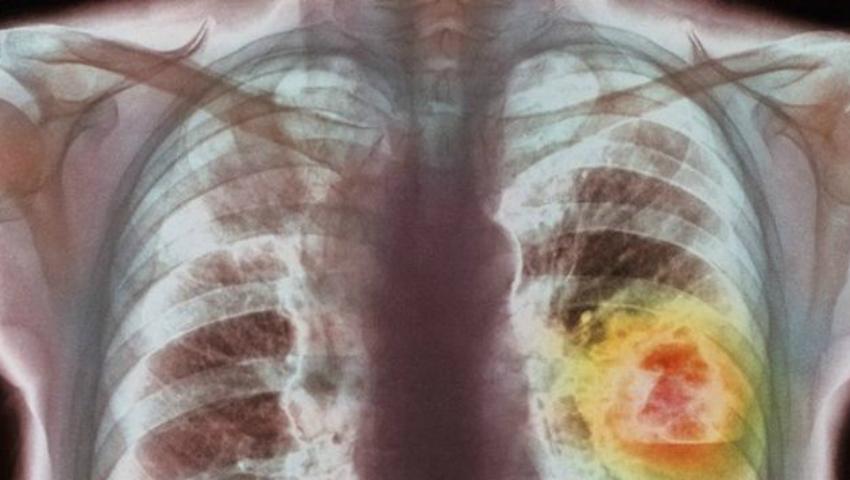

Numărul cazurilor de cancer creşte alarmant de la un an la altul, iar acest lucru îngrijorează autorităţile din sănătate. În Republica Moldova tumorile ocupă locul doi printre cauzele de deces în rândul populaţiei. Doar în anul 2014 au fost înregistrate 8860 de cazuri noi de cancer şi 5972 de persoane au decedat.

Cele mai frecvente cauze de deces prin cancer în Republica Moldova survin din cauza cancerului pulmonar, colorectal, hepatic, mamar şi gastric, iar apropape jumătate dintre bolnavi decedează din cauză că boala a fost depistată în stadii avansate de evoluţie.Din acest motiv, Ministerul Sănătăţii şi-a propus să implimenteze o serie de măsuri menite să reducă rata incidenţei cancerului în R. Moldova.Astfel, numărul bolnavilor care decedează din cauza cancerului trebuie să se reducă cu 7% până în anul 2025, acesta fiind obiectivul de bază al primului Programul Naţional de control al cancerului pentru anii 2016-2025, votat de guvern în aceste zile.Documentul elaborat de Ministerul Sănătății are drept scop creșterea calităţii serviciilor medicale de diagnostic, tratament şi îngrijiri, inclusiv paliative, pentru bolnavii de cancer, precum și prevenirea factorilor de risc şi monitorizarea acestei maladii în baza unor date statistice de calitate.Prin acest rrogram, Ministerul Sănătății mai urmărește reducerea cu 10%, către anul 2025, a incidenţei cancerului pulmonar, de piele, stomac, ficat, prostată, colorectal, cervical şi mamar.[blockquote-quoted],,Acest lucru va fi realizat prin controlul factorilor de risc comportamentali, precum fumatul, consumul de alcool, alimentaţia nesănătoasă sau lipsa activității fizice'', se arată în comunicatul Ministerului Sănătăţii.[/blockquote-quoted]În calendarul naţional de imunizări va fi introdus un nou vaccinDe asemenea, prezentul Program va dezvolta şi implementa un studiu de fezabilitate pentru introducerea vaccinului HPV în Programul naţional de imunizări, care va permite prevenirea cancerului de ficat.Un alt obiectiv al guvernului este sporirea cu 25% a ratei de depistare precoce a cancerului, în stadiile I și II, până în anul 2025. Prin urmare, va fi îmbunătăţită modalitatea de organizare şi prestare a screening-ului cancerului cervical, colorectal şi a serviciilor de depistare precoce a cancerului mamar.De asemenea, lucrătorii medicali, în special cei din asistenţa medicală primară, care sunt implicaţi în prestarea serviciilor de screening, vor beneficia de instruiri, în scopul fortificării capacităţilor şi abilităţilor profesionale.În plus, va fi revizuită organizarea serviciului oncologic la nivel naţional. Institutul Oncologic va fi dotat suplimentar cu dispozitive medicale și asigurat cu personal medical, fiind desemnat în calitate de Centru Naţional de Referinţă în Oncologie din Republica Moldova.  De asemenea, vor fi revăzute programele de instruire a specialităţilor în oncologie.Pacienţii cu cancer în stadii terminale vor beneficia de servicii paliative mai buneÎn cadrul Programului urmează să fie asigurat accesul la îngrijiri paliative şi servicii de reabilitare pentru pacienţii cu cancer în stadii terminale. Urmează ca această profesie să fie introdusă în Nomenclatorul specialităţilor din ţară, iar personalul medical, pregătit peste hotare în acest domeniu, să fie certificat în țară.Programul Național mai prevede crearea Registrului de Cancer, care să reprezinte o sursă sigură de date calitate şi de încredere, privind activităţile de prevenire, depistare precoce şi tratamentul cancerului.De asemenea, pentru prima data, Republica Moldova va avea Consiliul consultativ responsabil de monitorizarea şi evaluarea implementării intervenţiilor publice în controlul cancerului. Această structură va fi constituită din experți, care se vor ocupa de coordonarea programelor de screening şi acţiunilor realizate de diferiţi prestatori publici şi privaţi sau din asistenţa spitalicească şi primară.Programul Național de control al cancerului a fost elaborat cu suportul Organizației Mondiale a Sănătății și implementarea lui în următorii patru ani necesită resurse financiare în sumă de circa 1,6 milioane lei, banii fiind alocaţi din bugetului public naţional.